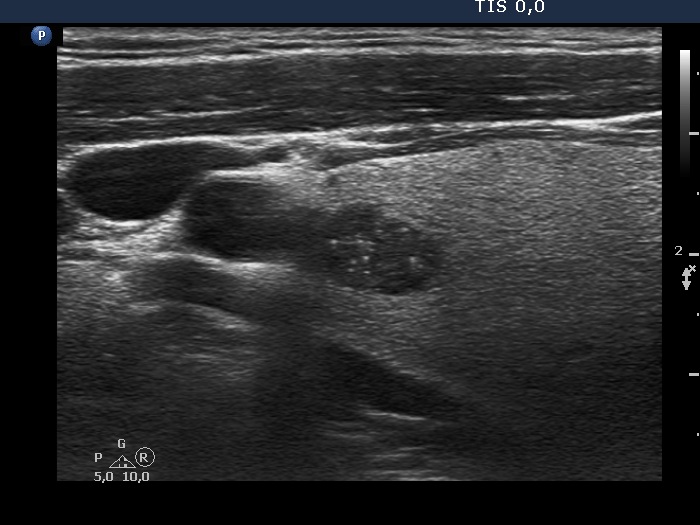

Intranodular hyperechogenic figures - case 975 (ultrasonographic picture 3)

Upper part of the right lobe, longitudinal view. The bright granules cannot be categorized other than microcalcifications.